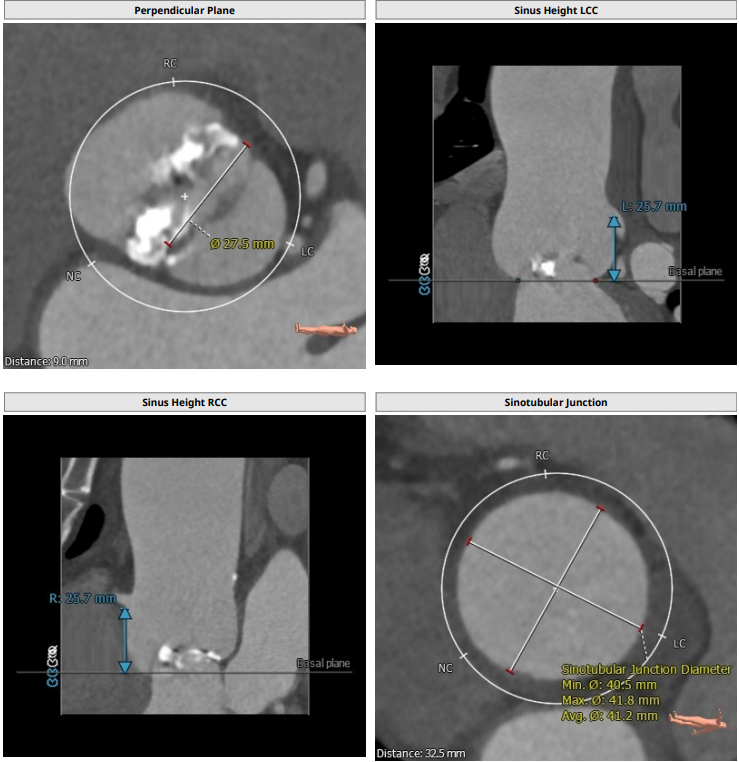

本例患者只有61岁,超声诊断低流速低压差AS,合并升主动脉扩张,CT下测量升主动脉超过50,原则上首选外科手术。但广东省人民医院大血管组会诊后考虑患者低流速低压差,行主动脉瓣和升主动脉置换术,手术风险极高,建议TAVR。从解剖上,瓣环流出道的大小分别是30、31,但瓣上结构是TYPE 0二叶瓣,重度钙化,联合部有钙化融合,瓣上短轴31,窦高度超过23,横位心,角度78°二叶瓣方向呈1点到7点方向。这种解剖做TAVR无疑挑战极大。对于低流速低压差的患者合并解剖挑战的病人,术前计划就是ecmo辅助下TAVR。考虑二叶瓣和重度钙化,目标瓣膜是29号,故用23号球囊预扩,尽量不破坏瓣上结构,另外考虑横位心,升主宽,破裂风险高,瓣膜跨瓣困难,故准备抓捕器辅助跨瓣。投照角度方面准备了瓣膜切线位(左肩),用来跨瓣和球扩,同时准备多一个右足位,这个角度下瓣环和人工瓣膜可以达到共平面,方便瓣膜定位。因为升主宽,横位心,主动脉迂曲,为减少破裂风险,没有选择plus。术中跨瓣遇到较大挑战,因为主动脉根部的角度大,普通的AL2,JR2,多功能导管均无法跨瓣,尝试直头导丝和弯头泥鳅也失败,最后是JL4加直头导丝成功跨瓣。预扩后瓣膜跨瓣尽管在抓捕器辅助下仍然非常困难,在反复尝试后侥幸跨瓣。瓣膜释放后位置偏深,但结合瓣膜角度,瓣周漏可以接受,压差消失,故未再行瓣中瓣。术中未发生停跳,故手术结束后撤去ECMO返回CCU。术后一个月随访EF值明显改善,患者自我感觉明显好转,虽然有中度瓣周漏,但是患者年轻,调整好心功能后,为以后外科置换升主动脉和主动脉瓣打下基础。

患者为type0二叶瓣,重度钙化,78度大横位心,左心明显扩大,EF值为21%,瓣环径为30.1,LVOT31.5,二叶瓣鱼嘴开口初短径为31,钙化融合至对侧为27.5,左右冠高度均为25.7,升主明显扩张。